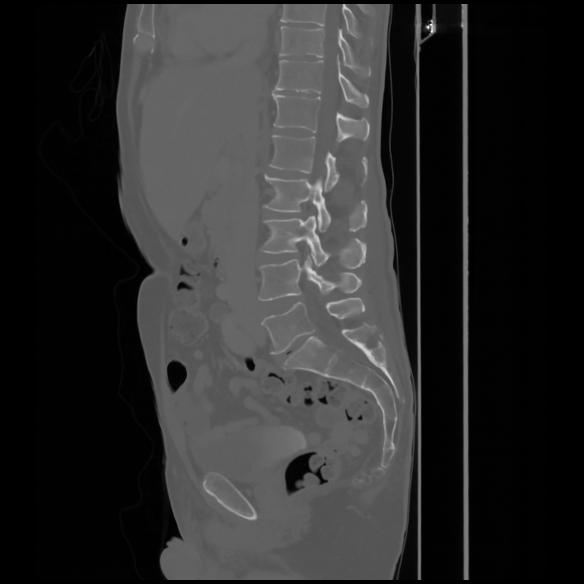

7 CUERPO,CE,Sagittal,3.000,CUERPO,Sagittal,